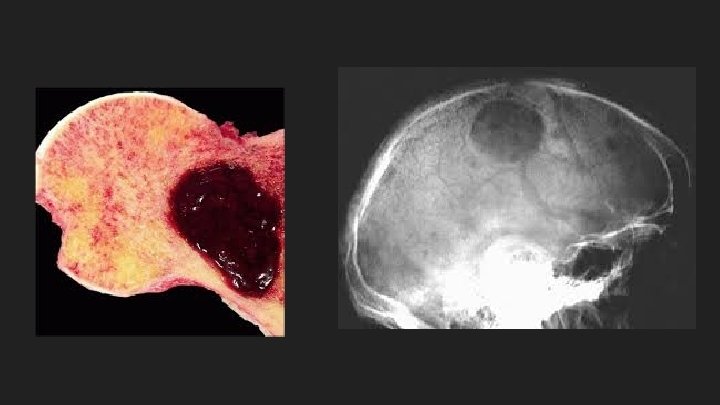

Bone Pain ● Due to the expanding population of plasma cells ● Most common symptom (70%) ● Precipitated by movement ● Bone disease: ○ Activation of osteoclasts and suppression of osteoblast ○ Lytic lesions (maybe palpable) ○ Hypercalcemia ○ Pathological fractures ○ Vertebral collapse – spinal cord compression

Radiographic Studies ● Skull ● Long bones ● Spine ● Lytic lesions ● Multiple ● Round ● Punched out ● Bone scan normal

Other Imaging studies ● Magnetic Resonance Imaging ● Thoracic and lumbar spine lesions ● Cord compressions ● Indicated when symptomatic ● Positron Emission Tomography